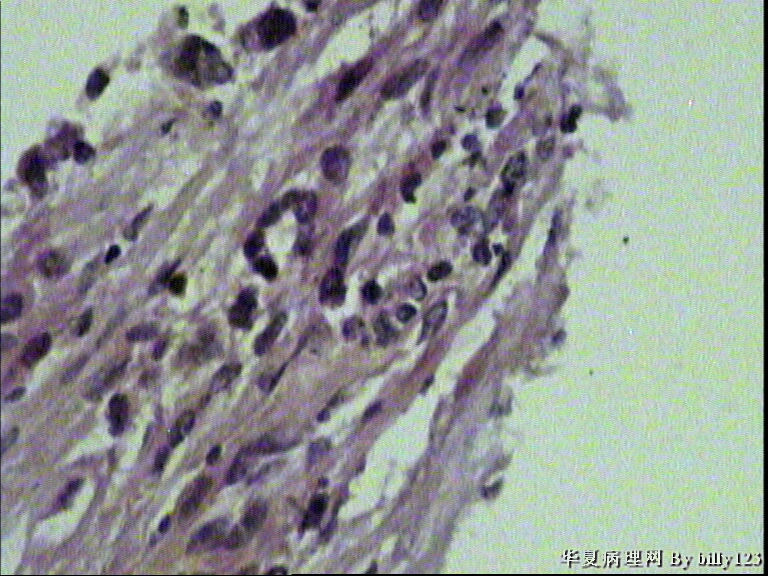

纤支镜活检,女性,75岁,请各位老师指教!

图3